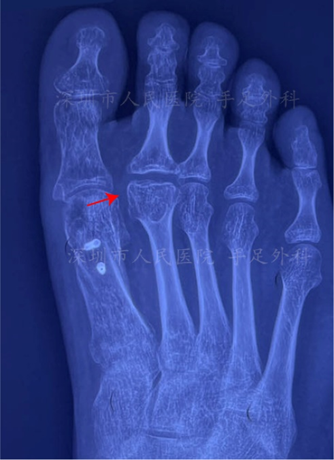

图6:拇趾籽骨

图7:籽骨骨折